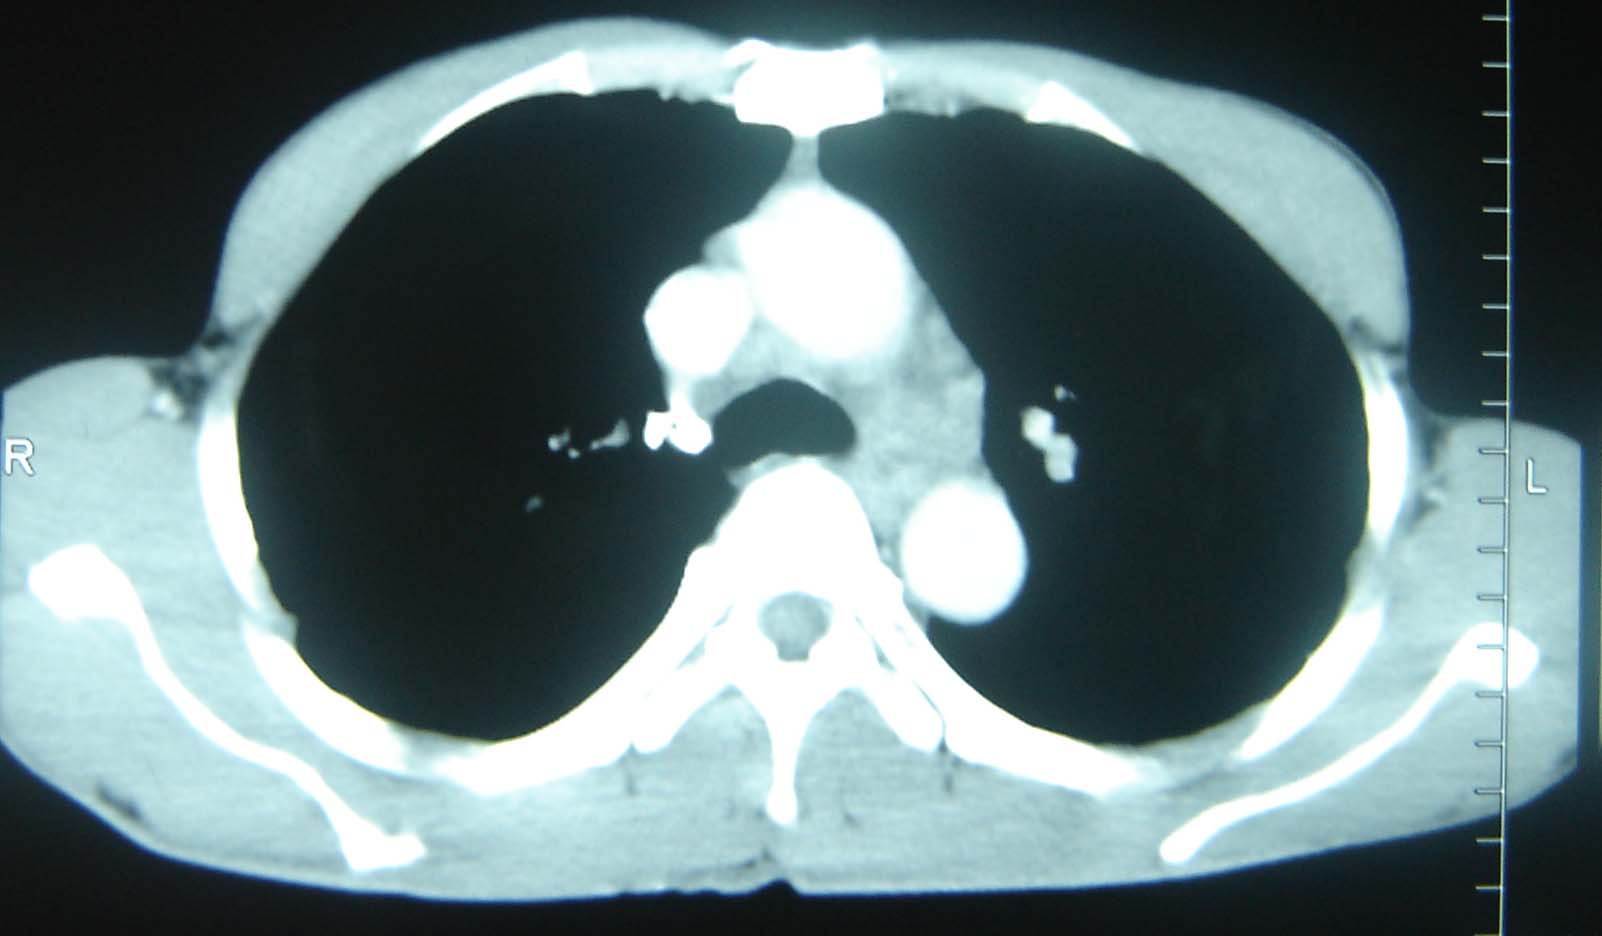

男 、43岁,咳嗽胸痛,装修工,平时接触粉尘较多,有吸烟史10多年,纤维支气管镜检查未发现异常,胃镜、腹部b超检查亦未发现异常,颈部淋巴结活检未发现肿瘤细胞。

不能排除转移,如果不能找到原发灶,只有短期随访。

结节病?转移瘤?

结节病。

转移瘤?

转移

1)考虑双肺及胸膜多发性转移瘤。2)肺气肿。

双肺结节病。